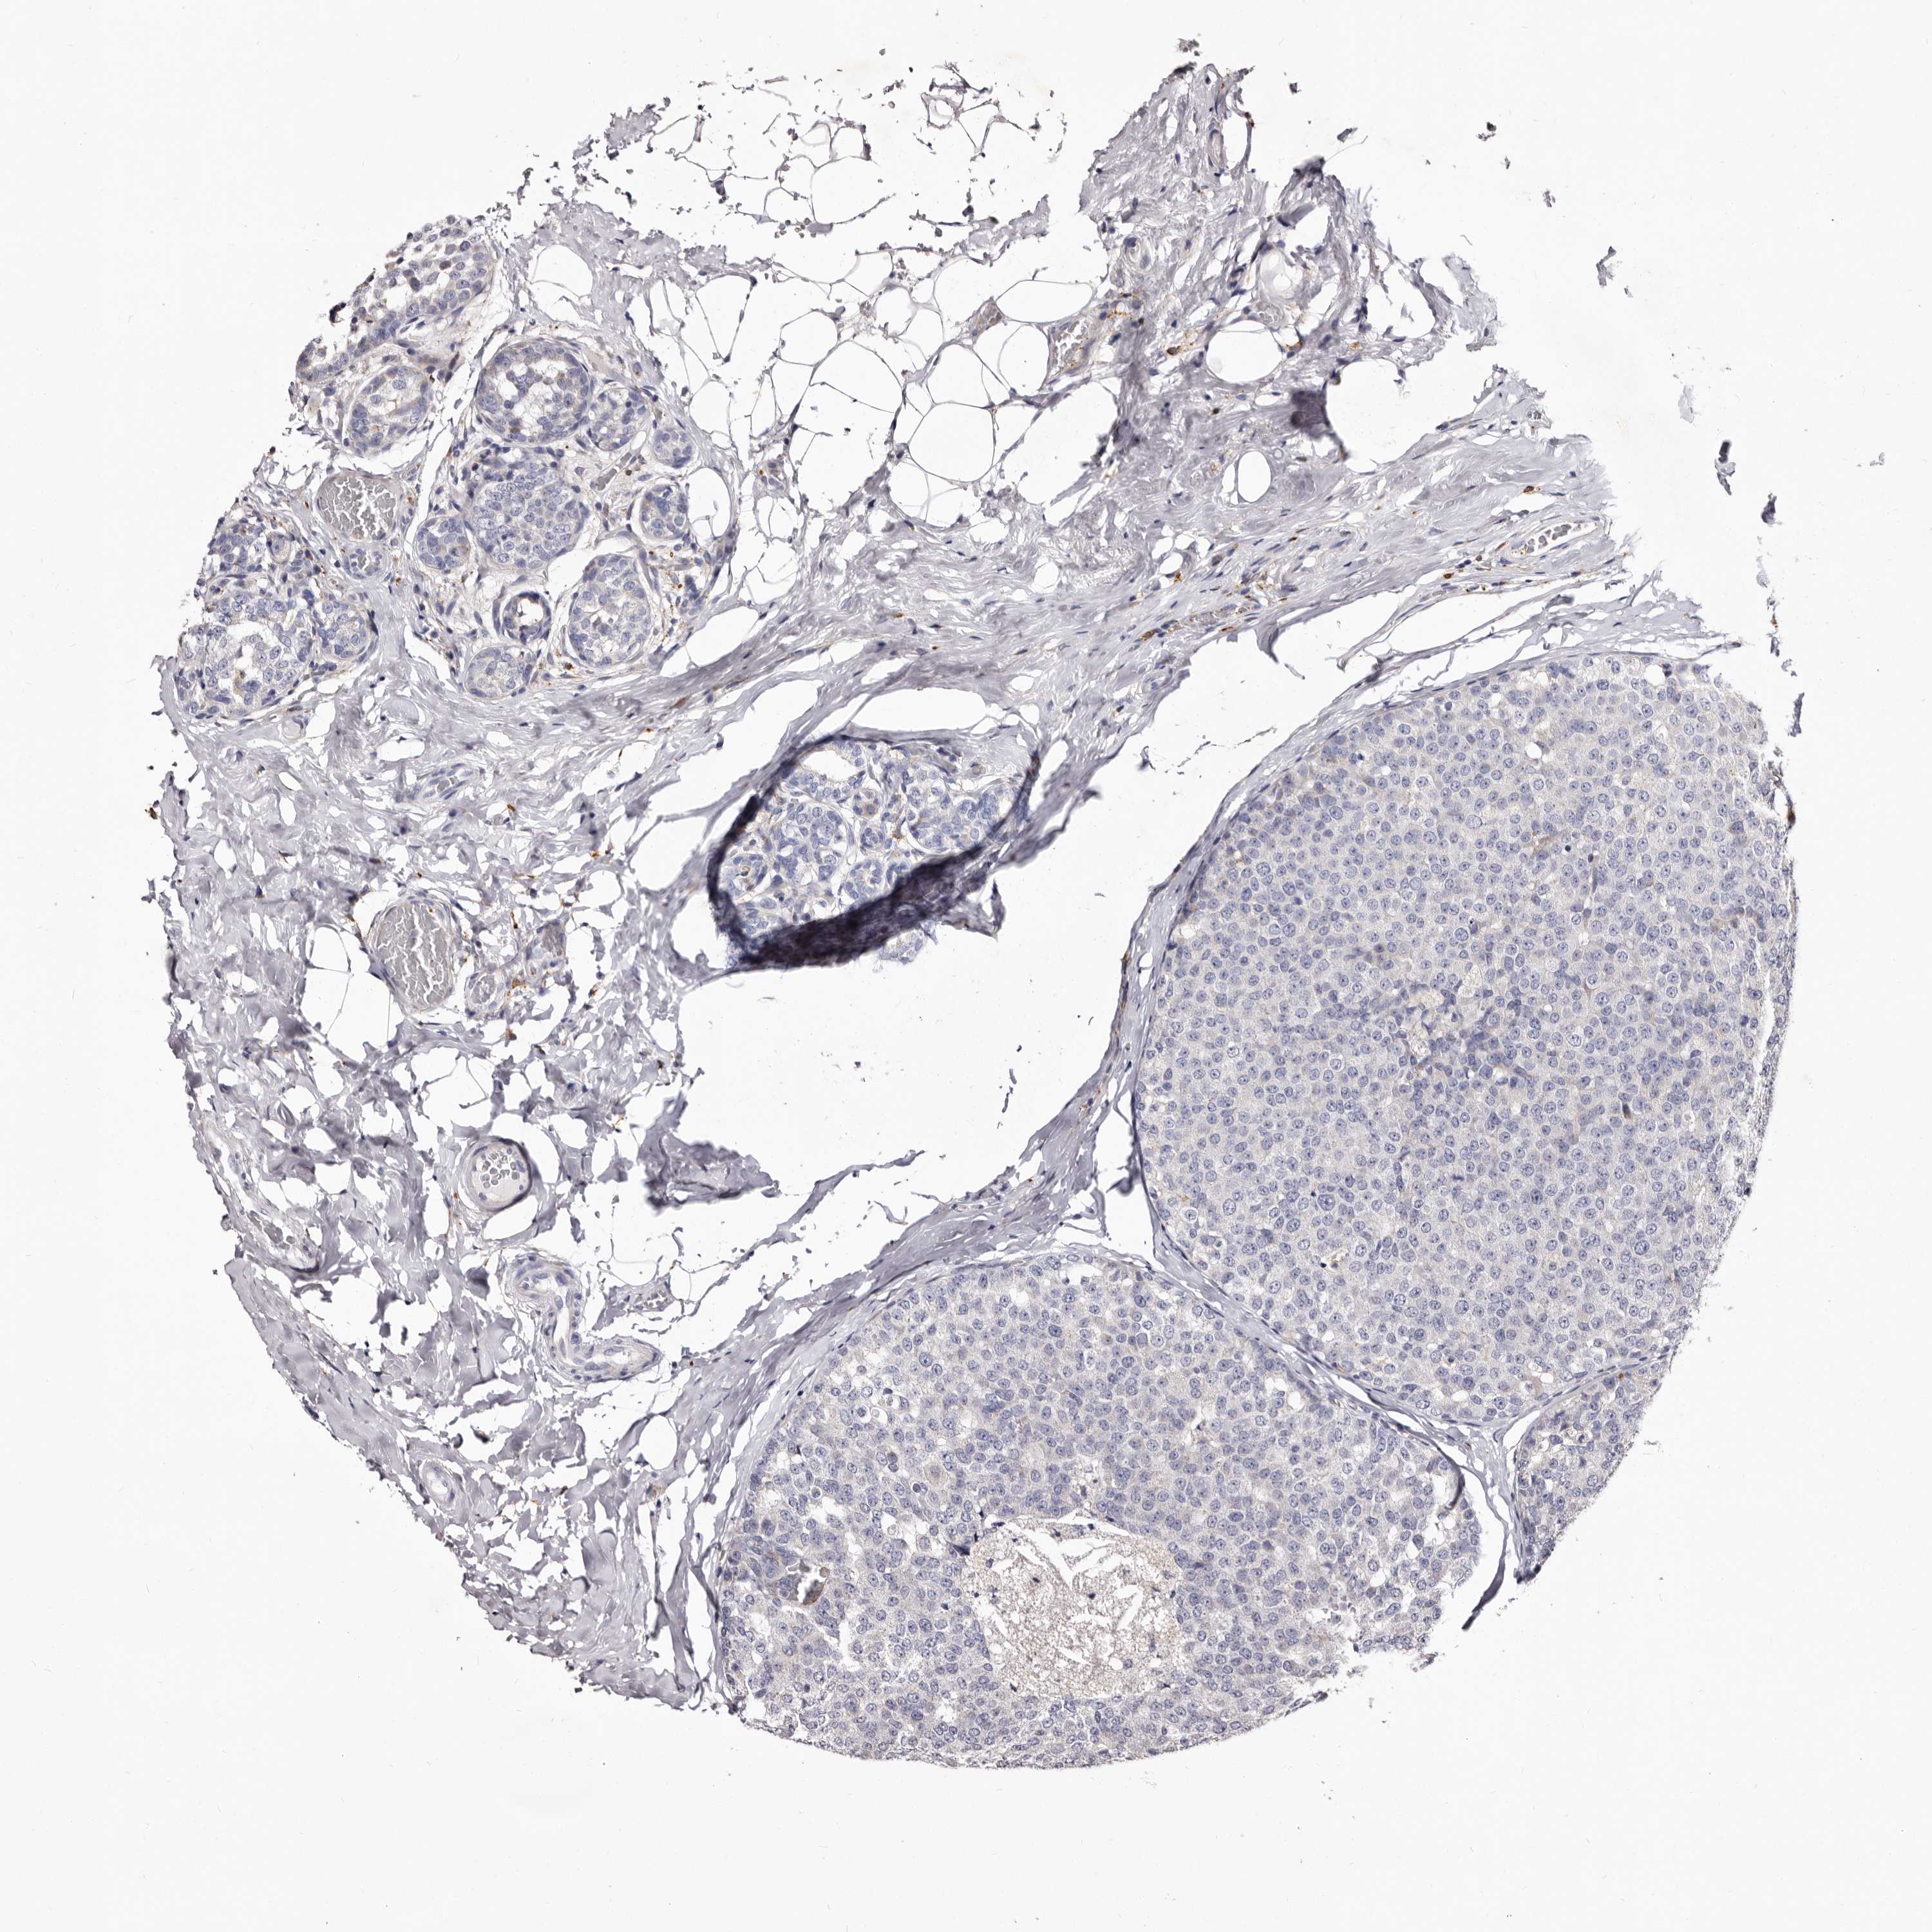

CANCER BREAST CANCER Show tissue menu

BRCA TCGA BRCA VALIDATION PROTEIN EXPRESSION

ANTIBODIES

AND

VALIDATION